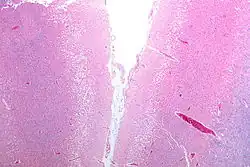

Cavitation at gross pathology of an old stroke in the left posterior parietal lobe

An autopsy of stroke may be able to establish the time taken from the onset of cerebral infarction to the time of death.

Cavitation 12 days or older